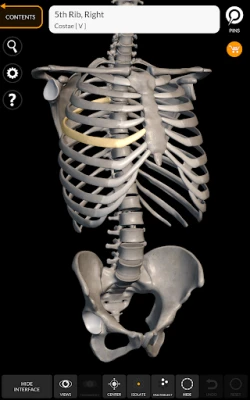

"Skeleton | 3D Atlas of Anatomy" is a next generation anatomy atlas in 3D which gives you availability of interactive highly detailed anatomical models!

Each bone of the human skeleton has been reconstructed in 3D, you can rotate and zoom in on each model and observe it in detail from any angle.

By selecting models or pins you will be shown the terms related to any specific anatomical part, you can select from 12 languages and show the terms in two languages simultaneously.

HIGHLY DETAILED ANATOMICAL 3D MODELS

• Skeletal System

• Accurate 3D modeling

• Surfaces of the skeleton with high resolution textures up to 4K

• Rotate and Zoom every model in the 3D space

• Division by regions for a clear and immediate visual of each structure

• Interactive Pin allow visualization of the term relative to every anatomical detail